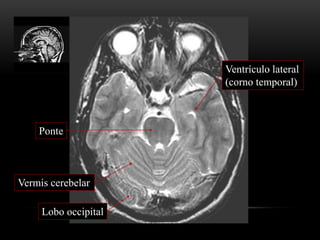

ANATOMIA TOPOGRÁFICA

Plano axial

Ponte

Ventrículo lateral

(corno temporal)

Lobo occipital

Vermis cerebelar